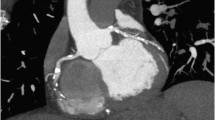

Multiple single- and multi-center studies have investigated the accuracy of coronary CT angiography for detecting anatomically significant stenosis with ≥50 % luminal narrowing in comparison with CCA as a reference. Across all published meta-analyses on the accuracy of coronary CT angiography using at least 64-slice CT systems with prospective triggering, the pooled sensitivity was 98.7 % (Fig. 2) (Menke et al. 2013; Meinel et al. 2015). The high sensitivity translates into an excellent negative predictive value of 95–100 %. A fully diagnostic coronary CT angiography that demonstrates no plaques or stenoses can exclude obstructive CAD with certainty (Fig. 3) (Meinel et al. 2015). In contrast to the high sensitivity and excellent negative predictive value, the reported specificity (89 %) and positive predictive value (60–80 %) remains lower (Menke et al. 2013; Arbab-Zadeh et al. 2012). The main reason for that is the abovementioned overestimation of coronary stenosis and resulting false-positive ratings in heavily calcified plaques.

A 61-year-old male patient with atypical chest pain. Curved multiplanar reformations of the LAD (a), LCX (b), and RCA (c) and 3D cinematic rendering (d) show no significant stenosis. Images were acquired with the high-pitch mode on a third-generation dual-source CT scanner; the estimated effective radiation dose was 0.4 mSv